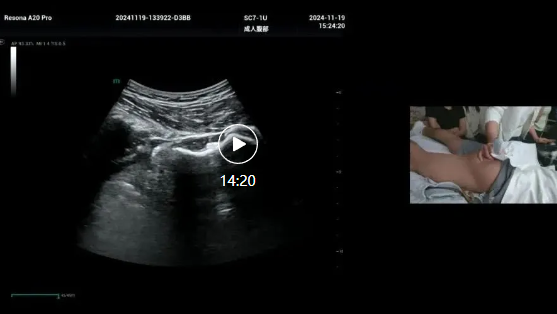

髋关节(后面)超声演示,张冰老师,广西区医院人民超声科,2024年

髋关节(后面)超声演示,张冰老师,广西区人民医院超声科,2024年